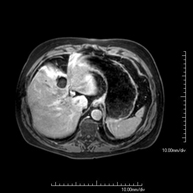

- RM d'Abdomen

Prova diagnòstica no invasiva que consisteix en l'obtenció d'imatges d'alta definició anatòmica de l'abdomen mitjançant l'ús d'un camp electromagnètic i ones de ràdio (amb un emissor i un receptor). No utilitza radiació ionitzant. En aquesta exploració s'inclouen el fetge, el pàncrees, la melsa, la via biliar, la vesícula biliar, les glàndules suprarenals, els ronyons, l'aorta abdominal, la vena cava inferior, l'estómac, el duodè, etc. En alguns casos caldrà emprar contrast paramagnètic (Gadolini) per caracteritzar les lesions. - RM Pelvis femenina

Prova diagnòstica no invasiva que consisteix en l'obtenció d'imatges d'alta definició anatòmica de la pelvis masculina mitjançant l'ús d'un camp electromagnètic i ones de ràdio (amb un emissor i un receptor). No utilitza radiació ionitzant. No requereix preparació prèvia. En algunes ocasions necessita l'ús de contrast paramagnètic (Gadolini) per caracteritzar les lesions. Aquesta prova permet valorar òrgans com la bufeta urinària, la unió entre els urèters i la bufeta, la pròstata, les vesícules seminals, la uretra i els ossos de la pelvis, entre d'altres. - RM de Fetge

Prova diagnòstica no invasiva que consisteix en l'obtenció d'imatges d'alta definició anatòmica del fetge mitjançant l'ús d'un camp electromagnètic i ones de ràdio (amb un emissor i un receptor). No utilitza radiació ionitzant. Es realitza per estudiar qualsevol lesió localitzada en el fetge. Normalment es requereix l'ús de contrast paramagnètic (Gadolini) per caracteritzar les lesions. És necessari realitzat la prova en dejú (6 hores). - RM de Ronyons